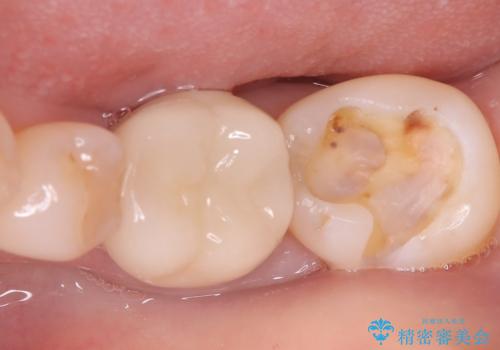

- 銀歯が取れたとのことで来院されました。中で虫歯が広がっている状態でした。材料の特徴を説明し、セラミックインレーでの修復となりました。

接着時にはラバーダム防湿を行いました。